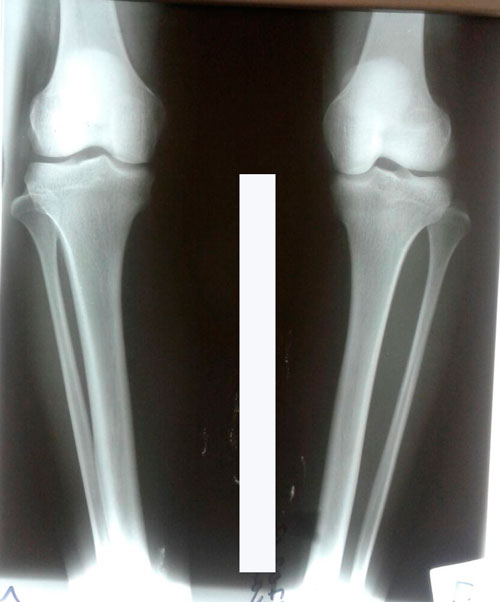

Исходник - 24 года.

Дата операции 19.07.2017г.

РЕНТГЕН ДО ОПЕРАЦИИ